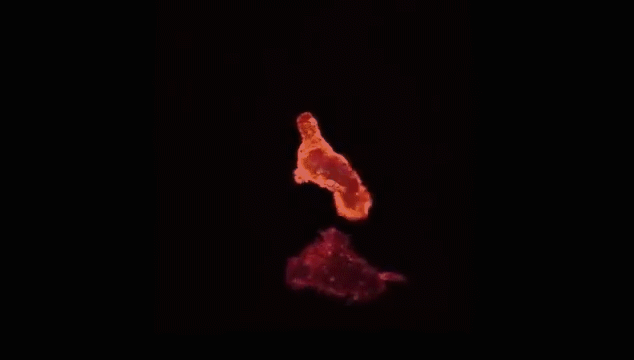

人体细胞总数在40~60万亿个之间,在这么多的细胞里,一些正常细胞由于物理、化学、病毒等致癌因子导致的原癌基因和抑癌基因突变后,就变成了癌细胞。一个正常人,每天会因各种原因产生6000个左右的癌细胞,而人体的免疫细胞则负责消灭癌细胞。美国细胞生物学会(ASCB)发布了一则微观大片,使用顶级的成像工具和技术,从免疫角度展示了人体中的一种免疫细胞T细胞杀死癌细胞的全过程。每个T细胞大约是人类头发直径的十分之一,它们在人体内不断巡逻,找出并杀死癌细胞或感染了危险病毒的细胞。当T细胞发现癌细胞时,通过分泌的毒素附着在癌细胞上,来检测、分辨正常细胞与癌细胞。查明之后,T细胞连接癌细胞,打破癌细胞外壁,向其表面引入毒性蛋白。一旦细胞毒素进入,癌细胞会逐渐衰弱、死亡。而T细胞继续在人体内巡逻,寻找下一个目标。其实除了上面提到的T细胞以外,身体里面还有很多免疫细胞在保护着我们,它们与癌细胞斗智斗勇,以抵御病毒保卫身体为终极目标。给大家分享几张免疫细胞“杀敌”的动图,来看看帅气的它们是如何英勇作战的:吞噬细胞在固有免疫中发挥重要作用,是清除致病微生物的重要免疫细胞。吞噬细胞包括两大类,即中性粒细胞(小吞噬细胞)及单核/巨噬细胞(大吞噬细胞)。两类吞噬细胞对入侵体内的微生物可极为快速的产生应答,尤以巨噬细胞的作用更为持久,是参与晚期固有免疫应答的主要效应细胞。NK细胞是T和B细胞并列的第三类淋巴细胞,不同于T、B细胞,它是具有直接杀伤靶细胞效应的一类淋巴细胞,靶细胞包括肿瘤细胞、病毒或细菌感染的细胞及机体某些正常细胞。NK细胞率先吹响战斗号角,以癌细胞头部为突破口发起进攻,癌细胞负隅顽抗NK细胞头部部队成功突破,大部队快速抵达战场,癌细胞瞬间瓦解NK细胞具有抗肿瘤、抗感染、免疫调节等功能,在病毒和寄生虫的抗感染免疫早期发挥重要作用。B细胞是体内产生抗体(免疫球蛋白)的细胞,B细胞也存在不同的亚群,主要执行体液免疫,也具有抗原提呈功能。通常情况下,人体的免疫系统可以高效地识别和消灭癌细胞,保证我们的身体健康。这些人体的天然“健康卫士”,绝对不会放过每一个逃逸的癌细胞。即便癌细胞成功逃逸进入血液,免疫细胞也会对癌细胞发起猛烈进攻。免疫细胞可穿过血管壁奔赴“战场”,向炎症和创伤组织进军、围剿。随着人类生命科学的不断发展,科学家们揭示了免疫细胞杀死癌细胞的作用机制,并证实了免疫细胞在对抗癌症上具有无可比拟的先天优势,根据这一特性,人类科学家探索出一系列通过补充T细胞、NK细胞、甚至使用CAR-T、CAR-NK等“大杀器”,来对抗癌症的免疫疗法。厉害了!我的免疫细胞!与病菌抗争的场面简直可以拍成一部精彩的战争电影了!想象一下,如果身体缺少它们每天顽强地抗敌的话,我们会怎样呢?应该连最基本的呼吸都难以做到了吧,毕竟空气中有那么多细菌,少了免疫细胞我们真没办法存活了......但是还是想跟大家说的一个真相是,免疫细胞虽然很强大,但是它们也会随着身体的老化而变得衰弱甚至死亡。因为少了免疫细胞的保护,身体对外来病毒的抵抗力就会变弱,人就会很容易生病。 |